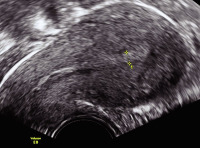

Tipps und Tricks im Gyn-Ultraschall: Das prämenstruelle und das menstruelle Endometrium

Journal für Gynäkologische Endokrinologie 2013; 7 (3) (Ausgabe für Österreich): 24-25 Journal für Gynäkologische Endokrinologie 2013; 7 (3) (Ausgabe für Schweiz): 33-34 Volltext (PDF) Abbildungen